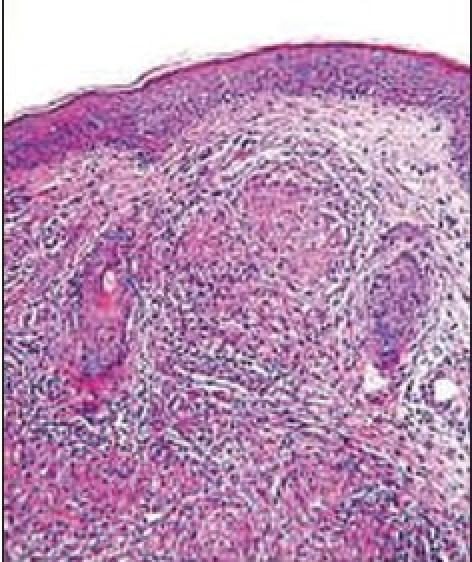

Extrapulmonary tuberculosis constitutes about 10% of all cases of tuberculosis, and cutaneous tuberculosis makes up only a small proportion of these cases. Despite prevention programs, tuberculosis is still progressing endemically in developing countries. Commonest clinical variant of cutaneous tuberculosis in our study was lupus vulgaris seen in 55% patients followed by scrufuloderma seen in 25% patients followed by orificial tuberculosis, tuberculosis verrucosa cutis, papulonecrotic tuberculid, and erythema induratum seen in 5% each. The commonest site of involvement was limbs seen in 50% patients followed by neck seen in 25% patients, face in 15%, and trunk in 10% patients. Maximum percentage of patients (55%) had duration of cutaneous tuberculosis between 6-12 months followed by 35% between 13-24 months, 5% had duration of cutaneous tuberculosis less than 6 months, and the rest 5% had duration more than 24 months. The commonest histopathological feature in our study was tuberculoid granuloma with epitheloid cell and Langhans giant cells seen in 70% patients, hyperkeratosis was seen in 15% patients and AFB bacilli were seen in 5% patients.

肺外结核约占所有结核病例的10%,而皮肤结核仅占这些病例中的一小部分。尽管有预防计划,但结核病在发展中国家仍呈地方性流行态势。在我们的研究中,皮肤结核最常见的临床类型是寻常狼疮,见于55%的患者,其次是瘰疬性皮肤结核,见于25%的患者,然后是腔口结核、疣状皮肤结核、丘疹坏死性结核疹和硬结性红斑,各占5%。最常受累的部位是四肢,见于50%的患者,其次是颈部,见于25%的患者,面部占15%,躯干占10%。最大比例的患者(55%)皮肤结核病程在6至12个月之间,其次35%在13至24个月之间,5%的患者皮肤结核病程少于6个月,其余5%病程超过24个月。在我们的研究中,最常见的组织病理学特征是结核样肉芽肿,伴有上皮样细胞和朗汉斯巨细胞,见于70%的患者,15%的患者有角化过度,5%的患者可见抗酸杆菌。